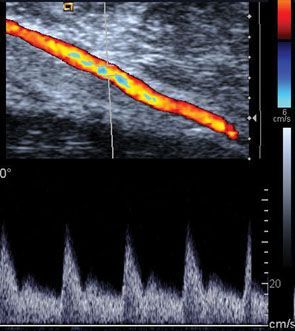

Допплер (Doppler) исследование может быть составной частью УЗИ диагностики сосудов или органов, в которых имеется кровоток. Допплер УЗИ – специальная техника ультразвукового исследования, которая оценивает кровоток через кровеносный сосуд, включая главные артерии тела и вены в брюшной полости, руках, ногах и шее. Допплер УЗИ может быть импульсным, цветным, тканевым, энергетическим. Но как бы он ни назывался – остается неизменным только одно: оценка кровотока через органы или сосуды.

Движение клеток крови вызывает изменение в отражении звуковых волн (Доплер-эффект). Компьютер собирает, обрабатывает эхо звуковых волн и создает реальную картину кровотока в сосудах или органах: измеряет скорость крови, записывает звуки, создает графики или цветные картинки.

При выполнении УЗИ с Допплер исследованием Вы можете фактически услышать звуки, подобные пульсу, поскольку проверяется и измеряется кровоток.